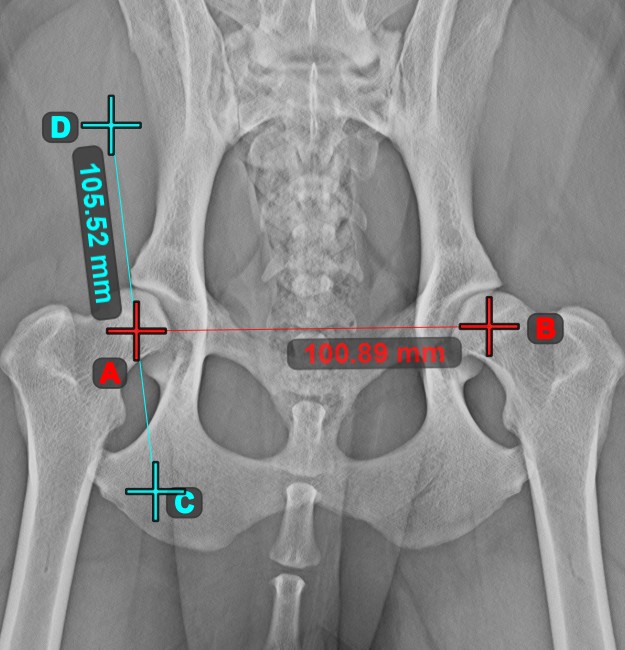

Erstellen Sie eine Linienmessung, um den Abstand zwischen zwei Punkten mit hoher Genauigkeit zu berechnen.

Wählen Sie das Werkzeug Linienmessung aus und weisen Sie es einer der verfügbaren Maustasten zu. Setzen Sie die Start- und Endpunkte in der Szene oder wählen Sie sie aus bereits vorhandenen Punkten im Bild aus. Der Abstand zwischen den beiden Punkten wird automatisch anhand der Standardkalibrierdaten oder der durch die Längenkalibrierung-Messung neu kalibrierten Daten berechnet.

Ändern Sie den Start- und Endpunkt mit dem Werkzeug Objekt auswählen/verschieben. Der Abstand zwischen den beiden Punkten wird automatisch neu berechnet.